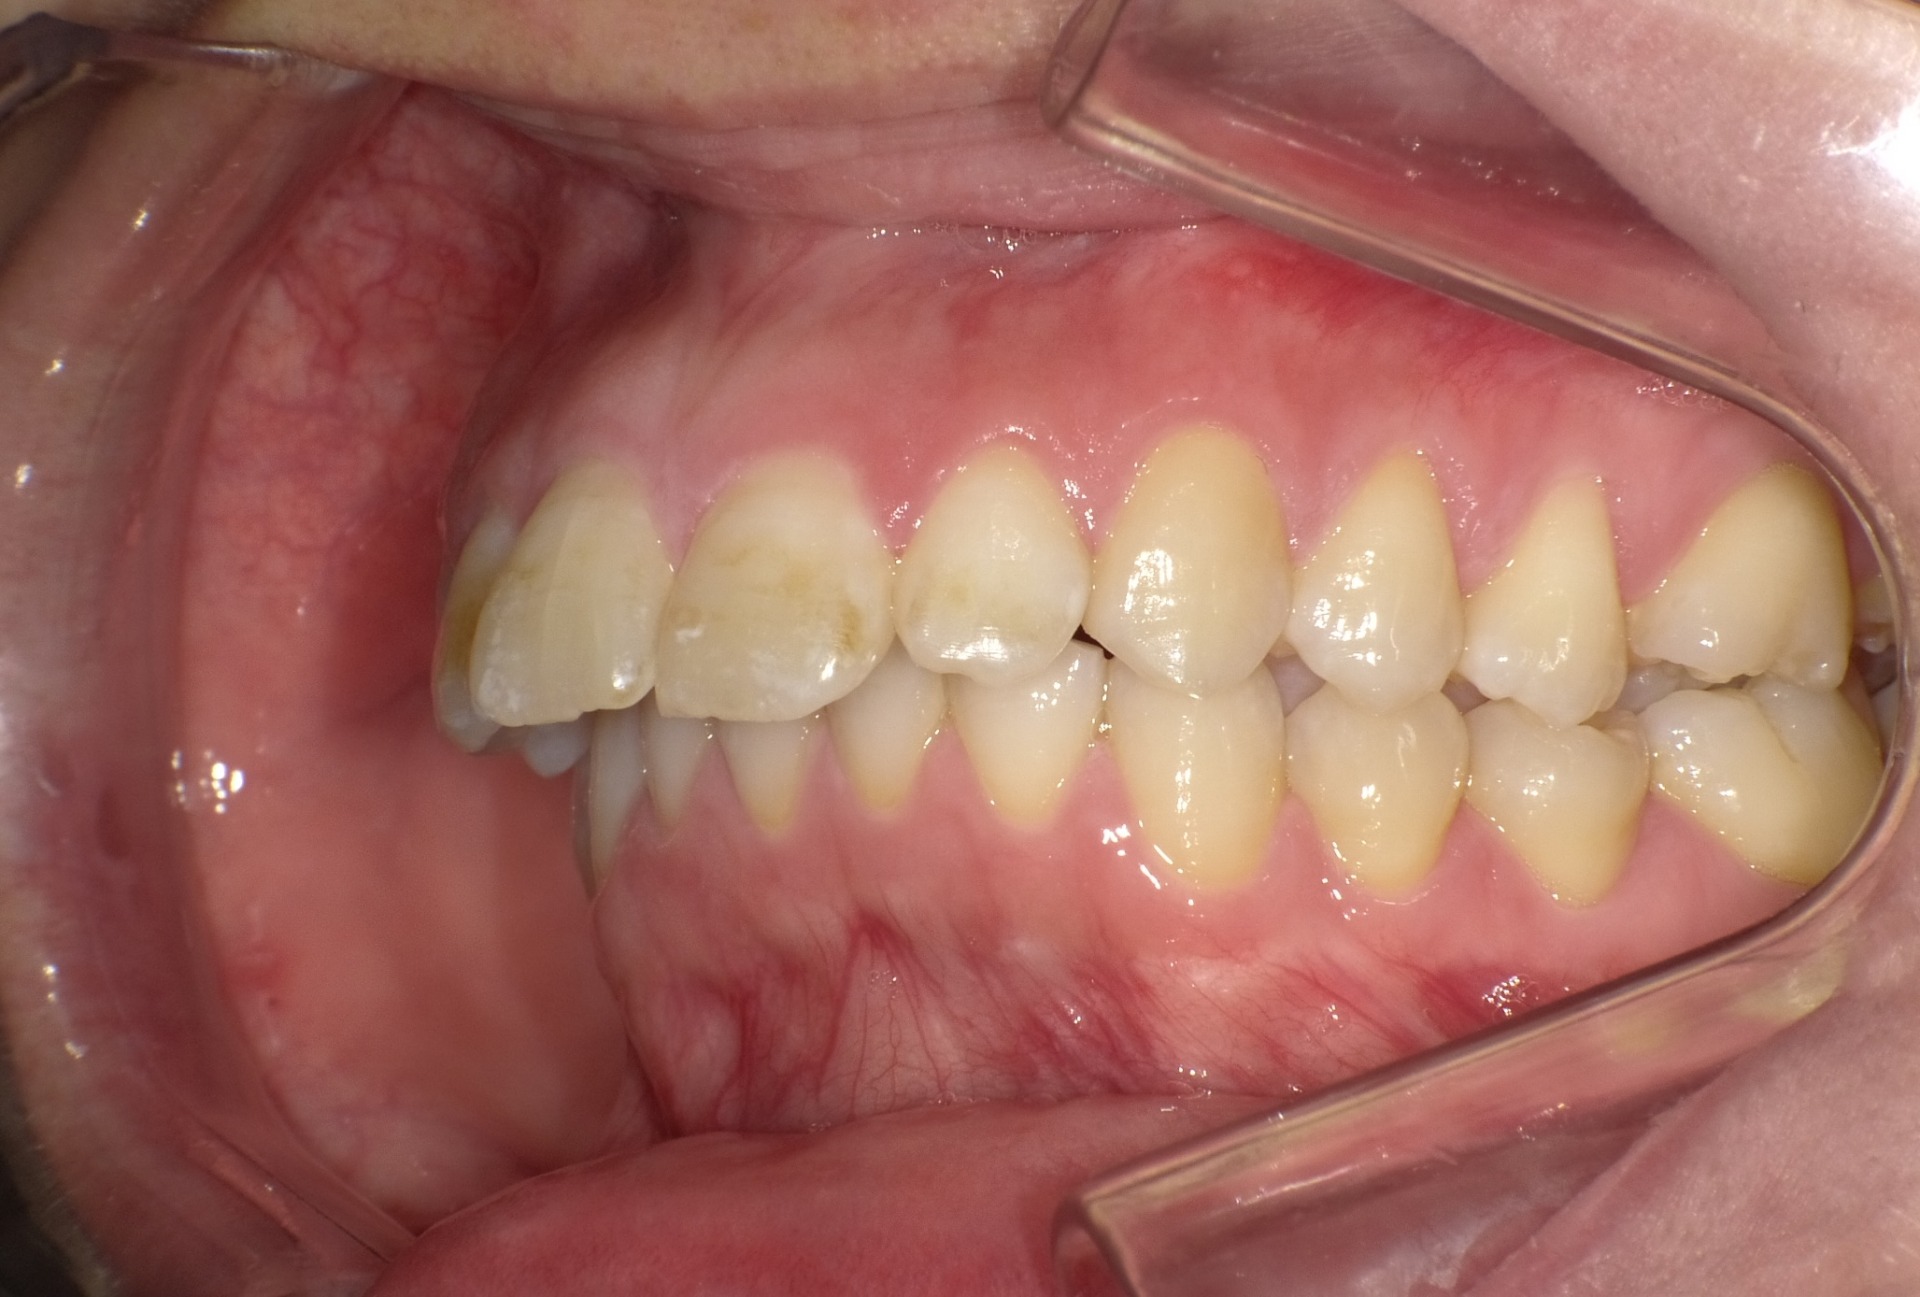

Before

| 症状 | 前歯が出ている |

| 通院目的 | 永久歯を抜かずに歯並びを治したい。 |

| 処置内容 | ディスタライザー・マルチブラケット装置 |